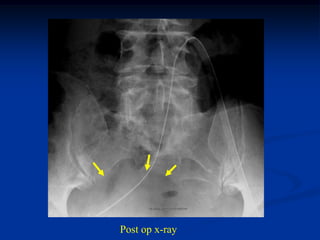

Cancellous autogenous

iliac chips placed

between tibia and

roughed up fibular